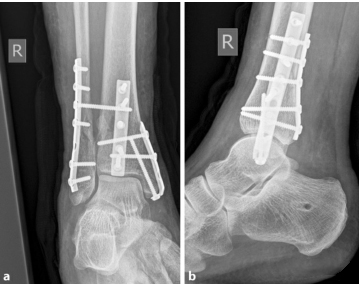

6). Стабилизация медиальной лодыжки особенно сложна в костях, пораженных остеопорозом. Пожилые пациенты чаще страдают переломами медиальной лодыжки, чем молодые пациенты. Натяжные ленты показали лучшие результаты при остеопорозе костей, небольших фрагментах или отрывных переломах; бикортикальные стягивающие винты большеберцовой кости также привели к большей стабильности и лучшим рентгенологическим и клиническим результатам; также доступна крючковая пластина, которая может обеспечить лучшие результаты и стабильность, особенно у пожилых пациентов (изображение ниже).